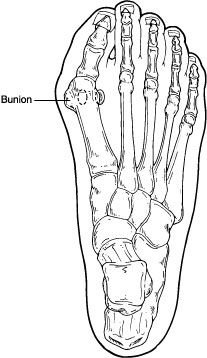

A bunion (also referred to as hallux valgus or hallux abducto valgus) is often described as a bump on the side of the big toe. But a bunion is more than that. The visible bump actually reflects changes in the bony framework of the front part of the foot. The big toe leans toward the second toe, rather than pointing straight ahead. This throws the bones out of alignment – producing the bunion’s “bump.”

Bunions are a progressive disorder. They begin with a leaning of the big toe, gradually changing the angle of the bones over the years and slowly producing the characteristic bump, which becomes increasingly prominent. Symptoms usually appear at later stages, although some people never have symptoms.

Bunions are readily apparent – the prominence is visible at the base of the big toe or side of the foot. However, to fully evaluate the condition, the foot and ankle surgeon may take x-rays to determine the degree of the deformity and assess the changes that have occurred.

A variety of surgical procedures is available to treat bunions. The procedures are designed to remove the “bump” of bone, correct the changes in the bony structure of the foot, and correct soft tissue changes that may also have occurred. The goal of surgery is the reduction of pain.